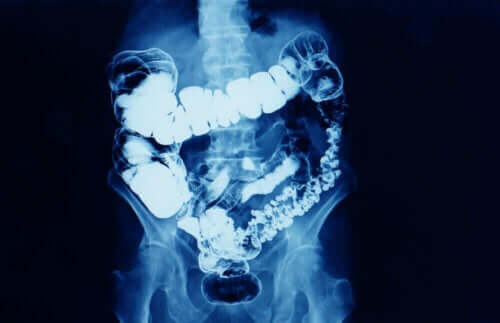

Generelt sett er forstoppelse når avføringens hyppighet reduseres. Forstoppelse er et symptom som betyr at tarmtransitten av en eller annen grunn reduseres.